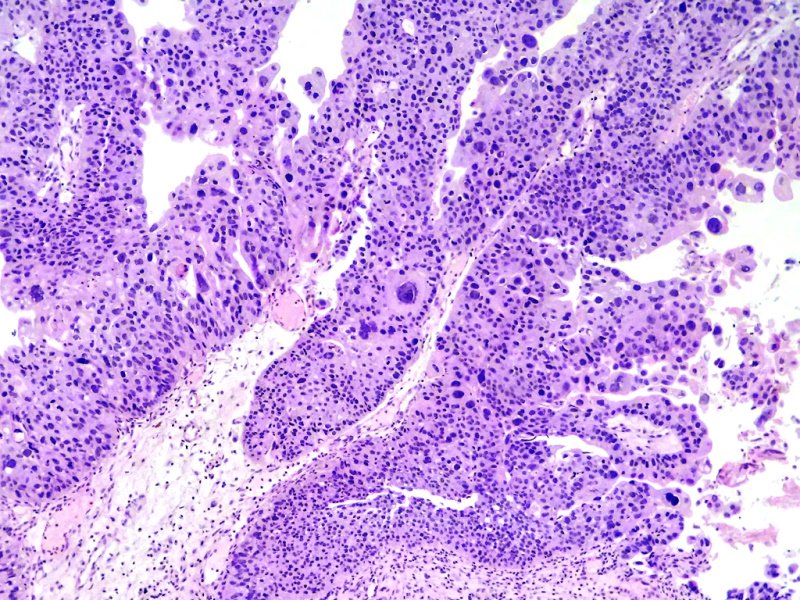

Vejiga. Carcinoma papilar urotelial invasor.